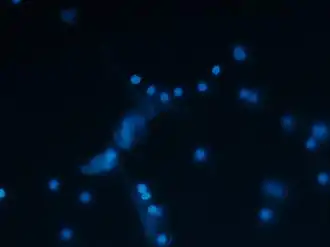

High-resolution scanning electron microscopy has shown that NETs consist of stretches of DNA and globular protein domains with diameters of 15–17 nm and 25 nm, respectively. These aggregate into larger threads with a diameter of 50 nm.[2] However, under flow conditions, NETs can form much larger structures, reaching hundreds of nanometers in length and width.[4]

Analysis by immunofluorescence corroborated that NETs contain proteins from azurophilic granules (neutrophil elastase, cathepsin G and myeloperoxidase), specific granules (lactoferrin), tertiary granules (gelatinase), and the cytoplasm; however, CD63, actin, tubulin and various other cytoplasmatic proteins are not present in NETs.[2][5]